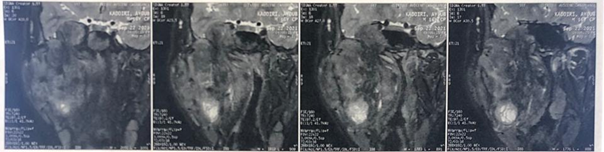

Inwardly and inferiorly, it infuses the hypopharynx

and the proximal part of the larynx, which remain permeable (Figure 5). Downwards and outwards, it

infiltrates the ascending branch of the mandible, with bone lysis (Figure 4). Anteriorly, it comes into

contact with the right maxillary sinus (Figure

6). Posteriorly, it fills the pre-stylial and retro-stylial space and

infiltrates the pre-vertebral muscles on the homolateral side. At the top, it

comes into contact with the floor of the orbit, with bone lysis of the anterior

and base of the skull, and infiltrates the homolateral temporal lobe (Figures 7 and 8). Below, it

infiltrates the right submandibular gland and the base of the tongue (Figure 5).

Figure 4: MRI on coronal section

showing the tumor infiltrating the ascending branch of the mandible, with bone

lysis

Figure 7: MRI on coronal section

showing the tumor that comes into contact the floor of the orbit

Figure 8: MRI on coronal section

showing the tumor infiltrating the base of the skull, and the homolateral temporal lobe